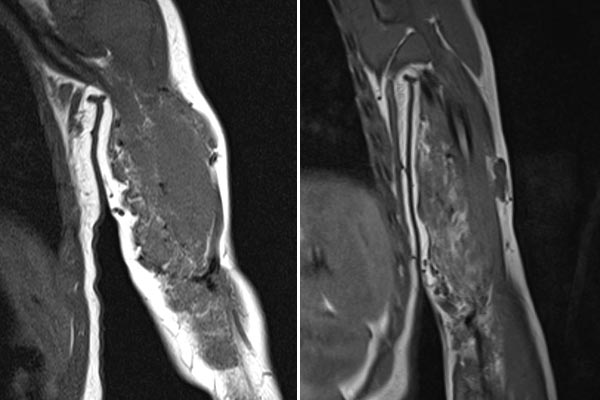

To further confirm the differential diagnosis, the child also underwent MRI, shown here in a coronal, T2-weighted, fat-suppressed STIR sequence. The tumor is highly hyperintense (white) and sharply demarcated from surrounding tissue. It penetrates all tissue planes and centrally contains signal-free areas, so-called flow voids, as a sign of strong arterial perfusion.

MRI was again performed to further clarify the differential diagnosis. A coronal, T2-weighted, fat-suppressed STIR sequence is again shown here. The tumor is now slightly less hyperintense, suggesting a slightly higher fat content in this fat-suppressed sequence. Perfusion has also decreased somewhat, with visibly fewer flow voids than in the previous MRI.

Comparison of coronal T1-weighted MRI sequences from February 2019 (left) with September 2021 (right). In these T1-weighted images, fat is shown as hyperintense (white). In the right image, it is easy to see that the amount of fat in the tumor has increased over time. This is typical of an infantile hemangioma that is partially in involution.